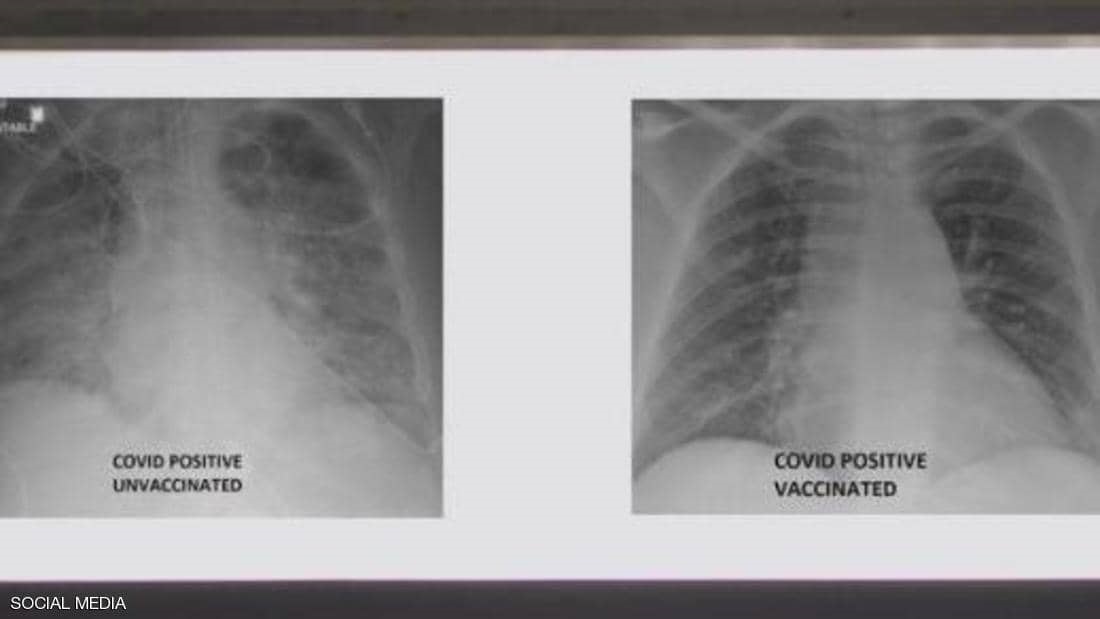

ملقح وغير ملقح.. صور الأشعة تكشف أثر كورونا على الرئتين

نشر الطبيب العربي في الولايات المتحدة، غسان كمال، صورة تظهر الفرق بين رئتي شخص جرى تطعيمه ضد فيروس كورونا ورئتي شخص آخر لم يتلق التطعيم، مشيرا إلى أن الاثنين أصيبا بفيروس كورونا.